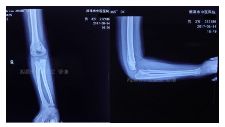

外院片如下:

简要病史:跌倒致左肘部畸形、肿痛、活动受限,就诊于当地医院,拍片诊断为肱骨髁上骨折,行手法复位,石膏固定,对位欠佳,转来我院。

治疗经过:入院行四步复位法手法整复,小夹板外固定